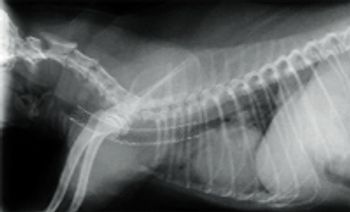

Most commonly, tracheal collapse occurs in middle-aged to old dogs including Yorkshire terriers, Pugs, Chihuahuas, Pomeranians, Maltese, as well as Miniature and Toy Poodles.